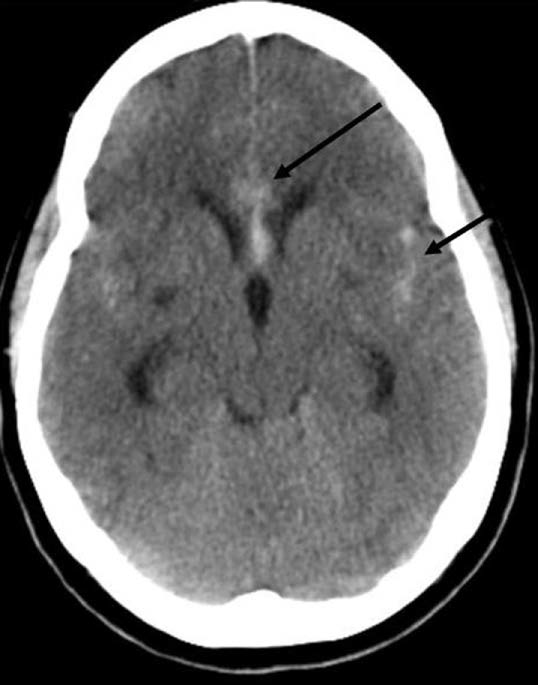

3-2. noncontrast brain CT : SAH가 의심되는 환자에서 가장 먼저 시행해야 할 검사이다.

- 증상 발생으로 부터 6~12시간 이내 촬영한 경우 민감도가 98%에 이른다.

- thunderclap HA 발생한 지 6시간 이내 환자에서 정상 brain CT 소견과 함께 정상 신경학적 검진소견은 SAH를 배제하는데 굉장히 민감하다. (SAH가 아니라 생각해도 무방!)

- 두통 발생 24시간 경과된 시점부터는 brain CT의 민감도가 떨어진다. 24시간에 91~93% 민감도, 1주 정도 지난 경우 50% 정도의 민감도를 갖는다.

- CT angiography나 brain MRI를 보조적인 수단으로 사용할 수도 있다.